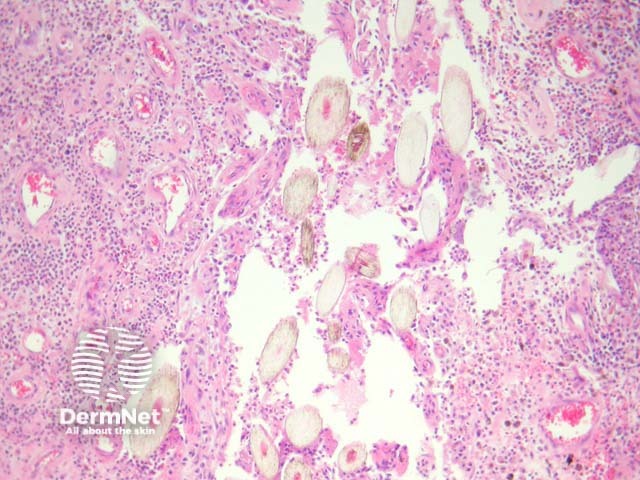

Sections show a dense inflammatory reaction usually occupying the entire dermis with erosion and ulceration of the overlying epidermis (figure 1). Free hair shafts are often seen coursing through the inflammatory focus (figure 2, arrow). Often, the free hair shafts are seen in clusters (figure 3). Dye used to outline the sinus tract for the surgeon may sometimes be seen. Surrounding the free hair shafts is a polymorphous infiltrate which may be rich in plasma cells and lymphocytes (figure 4). Foreign body-type giant cells and neutrophilic abscesses are also commonly observed.

Figure 2

Figure 3